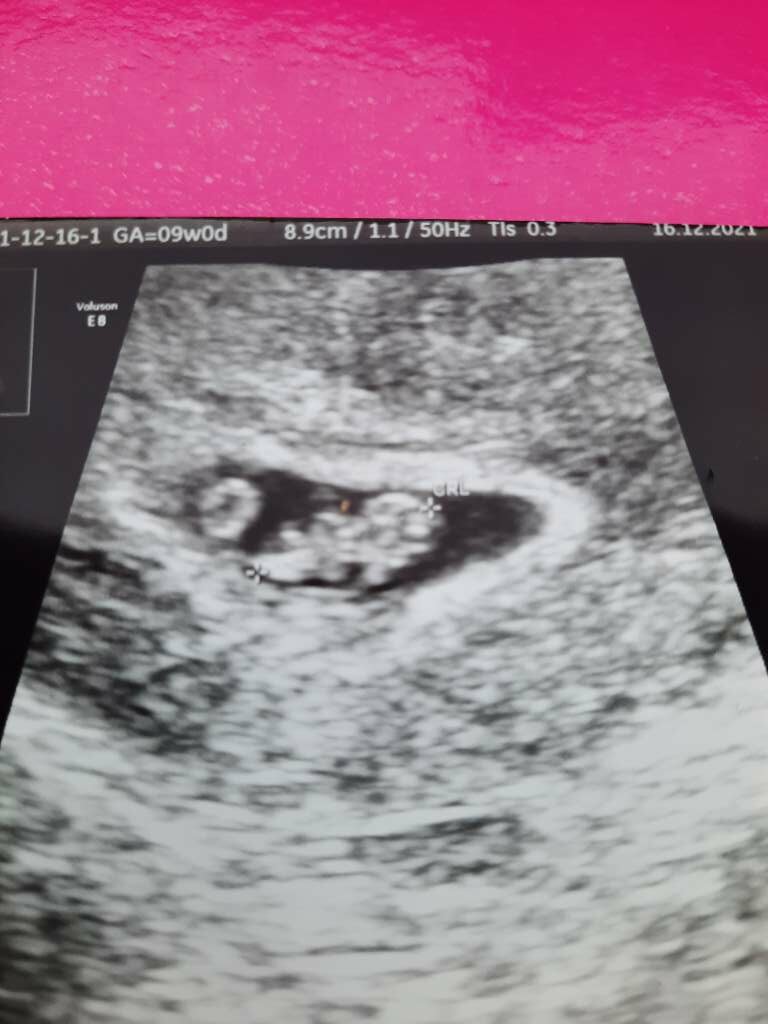

Oto człowiek! Całe 1,5 cm ❤❤❤

Załączniki

• 41c34b88-f712-451f-8ebd-e6ba0c17e0bd.jpg

41c34b88-f712-451f-8ebd-e6ba0c17e0bd.jpg

64 KB · Wyświetleń: 101